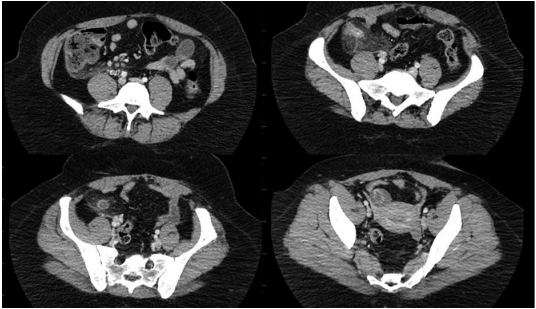

20000 leucócitos/mL (VR 0 – 10000). Realizou o exame a seguir.

(Arquivo pessoal; imagem usada com autorização)